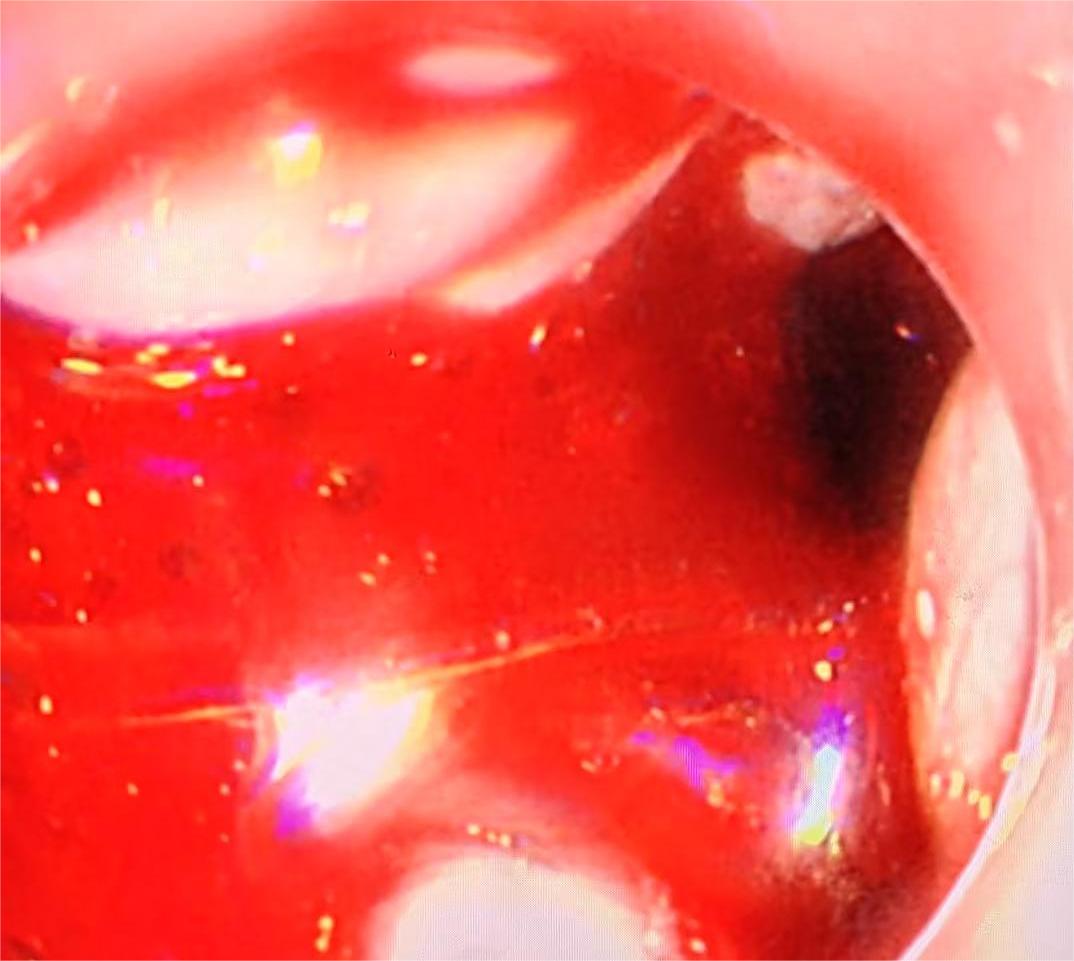

• 超声内镜引导下胃旁曲张静脉精准断流术治疗食管胃静脉曲张出血的疗效分析(附20例报告)

2025, 31(8):85-90. DOI: 10.12235/E20250036

摘要 (153) HTML (42) PDF 5.38 M (98) 评论 (0) 收藏

摘要:目的 探讨超声内镜引导下胃旁曲张静脉精准断流术治疗食管胃静脉曲张出血的疗效。方法 回顾性分析2024年1月1日-2024年12月31日于该院接受超声内镜引导下胃旁曲张静脉精准断流术治疗的20例肝硬化食管胃静脉曲张出血患者的临床资料,并评估治疗效果。结果 20例患者均顺利完成超声内镜引导下胃旁曲张静脉精准断流术;注射组织胶联合置入弹簧圈(16例)和单独注射组织胶(4例)均成功阻断胃旁来源的曲张静脉;所有患者均未发生穿孔、食管贲门狭窄、大出血、败血症和异位栓塞。1例单独注射组织胶的患者,术后胃旁曲张静脉少许渗血,经降低门静脉压力治疗3 d后好转,另1例单独注射组织胶患者,术后出现低热,抗感染3 d后体温恢复正常。结论 超声内镜引导下胃旁曲张静脉精准断流术治疗食管胃静脉曲张出血的临床疗效好,异位栓塞、大出血、感染和穿孔等并发症少,但仍需要密切随访,观察胃旁曲张静脉的排胶问题。